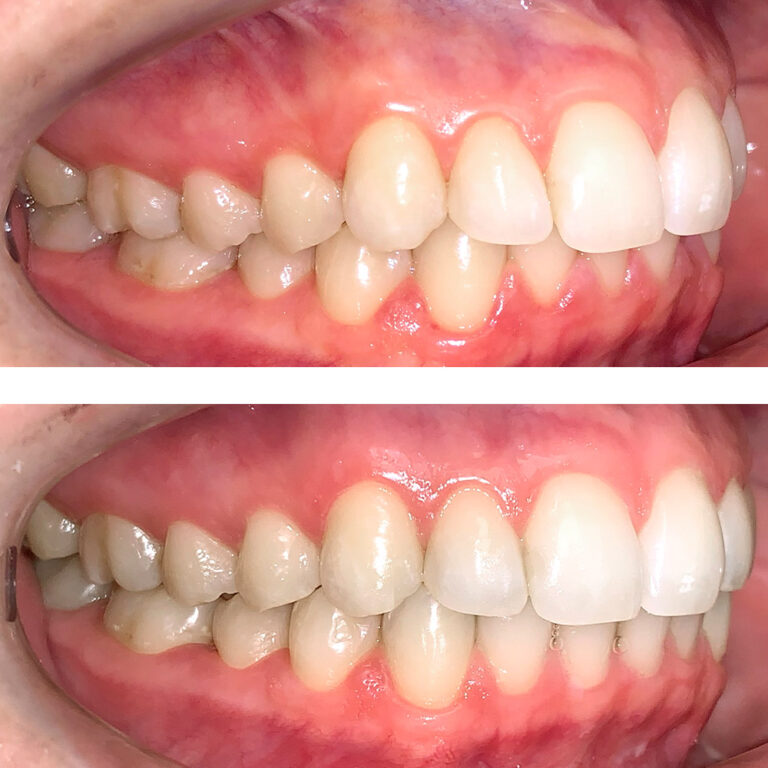

Кейс 11

Акинфиева Анна Владимировна

Количество кап ВЧ 12

Количество кап НЧ 16

ДО

ПОСЛЕ